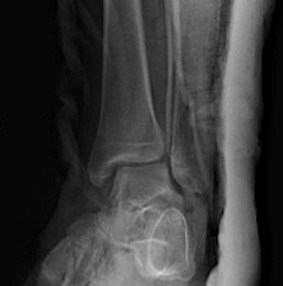

Fracture patterns

| Lateral malleolar fractures | Medial malleolar fractures | Bimalleolar fractures | Trimalleolar fractures |

Weber A - below syndesmosis Weber B - at syndesmosis Weber C - above syndesmosis |

Uncommon |

Fibular + medial malleolus Bimalleolar equivalent - fibular + deltoid ligament Fibular + posterior malleolus |

Fibular fracture + Medial malleolus fracture + Posterior malleolus fracture |